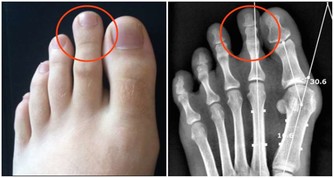

3. 關節炎症

關節炎很難好,但是如果每周堅持用生薑泡腳2-3次,兩個多月關節炎就能完全好,泡腳時加上點食鹽效果更好。